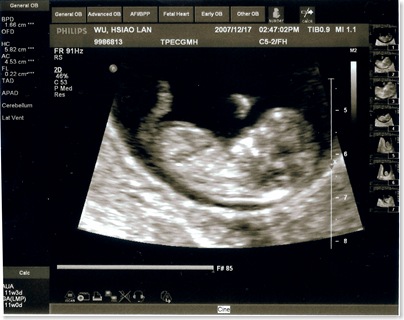

| 地點 | 12/28汐止吳婦產科 | 普通掛號, 超音波 |

| 週數 | 13週 | 這時你如果用手輕輕在腹部碰觸,胎兒就會蠕動起來,但你仍然感覺不到胎兒的動作。 胎兒的神經元迅速地增多,神經突觸形成,胎兒的條件反射能力加強,手指開始能與手掌握緊,腳趾與腳底也可以彎曲,眼瞼仍然緊緊地閉合。 |

| 身長 | 6.4cm | OK |

| 心跳 | 150下/分鐘 | OK |

花了150塊就照了這一張超清楚的照片

醫生也細心地講解各部位的發育

小baby還一邊揮舞著小手 看起來也像是在吸手指..

從右邊的數據可以看到頭臀長己經有6.4公分了

嗯.. 不錯

有乖乖在長大

每次照完超音波我們都很high.. 這次照得超清楚~~ 真好!!